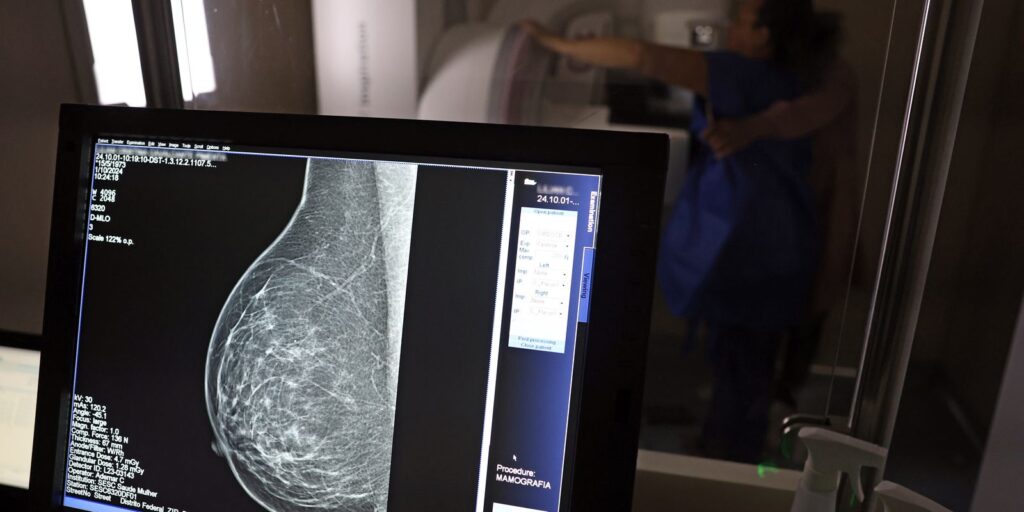

O Ministério da Saúde passou a recomendar o acesso a mamografia, via Sistema Único de Saúde (SUS), para mulheres de 40 a 49 anos – mesmo que não haja sinais ou sintomas de câncer de mama. De acordo com a pasta, a faixa etária concentra 23% dos casos da doença, e a detecção precoce aumenta as chances de cura.

Até então, a orientação era que o exame fosse feito a partir dos 50 anos.

A medida faz parte de um conjunto de ações anunciadas nesta terça-feira (23) voltado para a melhoria do diagnóstico e da assistência. A recomendação para mulheres a partir dos 40 anos é que o exame seja feito sob demanda, em decisão conjunta com o profissional de saúde.

As mamografias via SUS em pacientes com menos de 50 anos, de acordo com a pasta, representam 30% do total, o equivalente a mais de 1 milhão apenas no ano de 2024.

Os números mostram que, em 2024, cerca de 4 milhões de mamografias para rastreamento e 376,7 mil exames diagnósticos foram realizados no SUS.